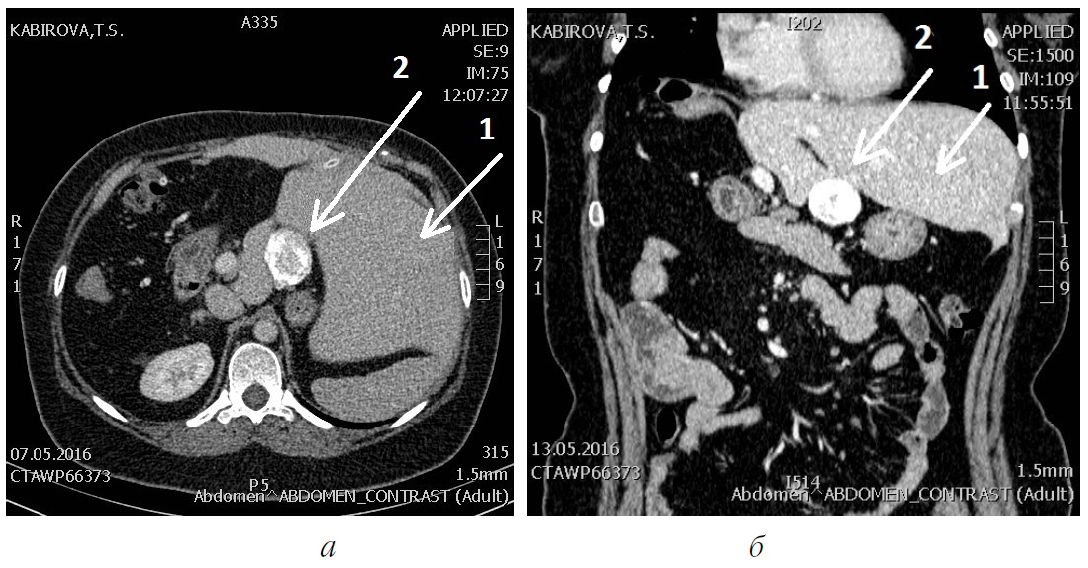

В настоящее время при личном осмотре 08.02.2018 состояние пациентки расценено как удовлетворительное. При контрольном исследовании на обзорной рентгенографии грудной клетки в двух проекциях от апреля 2017 г.: «...легочные поля чистые, усилен рисунок корня правого легкого ... Заключение: патологических изменений не выявлено». При контрольном исследовании от мая 2016 г. на компьютерной томографии брюшной полости отмечено, что « ...после правосторонней расширенной гемигепатэктомии ... между задним краем левой и хвостатой долей сохраняется округлое, частично петрифицированное образование с четкими

контурами, не накапливающее контрастное вещество, размерами 20×11×17 мм – остаточный альвеококк? В задних отделах правого купола диафрагмы сохраняется тканый участок с наличием петрификатов – остаточный альвеококк? В воротах печени определяется линейная гиперденсивная структура – дренаж. Заключение: состояние после правосторонней расширенной гемигепатэктомии по поводу альвеококка, ... СКТ-признаки викарного увеличения левой доли печени» (рис. 1).

Рис. 1. Компьютерная томография брюшной полости пациентки К.: а – в аксиальной проекции; б – во фронтальной проекции; 1 – викарно увеличенная левая доля печени; 2 – петрифицированный остаточный узел альвеококка